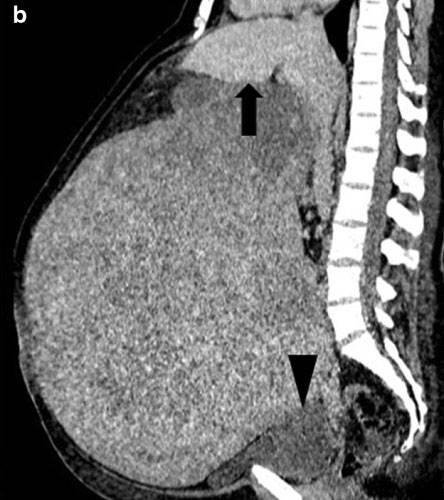

독일 UKSH(Universitatsklinikum Schleswig-Holstein) 대학병원 의료진은 46세 독일 여성 A씨가 15년간 자궁 출혈이 계속되고 복부가 점점 커지는 증상이 지속됐다며 산부인과를 찾았다고 밝혔다. 한 달에 생리를 여러 번 하고, 한 번 생리할 때 출혈량이 과다한 문제도 있었다. 전에도 병원을 몇 번 방문했지만, 당시 영상 촬영 등 철저한 검사를 하지 않아 종양이 발견되지 않았다. 하지만 UKSH 대학병원 의료진 진찰 결과, 복부가 과도하게 확대되고 늘어져 있었으며 양쪽 옆구리가 무언가로 가득차 있는 게 확인됐다. CT 촬영을 했더니, 거대한 크기의 종양이 발견됐다. 의료진은 수술로 종양을 제거했고, 종양 크기를 측정한 결과 부피가 무려 52cm x 37xm x 34cm에 달했고, 무게는 16.4kg이었다. 전체는 양성이 자궁근종이었으며 암은 아니었다. 다행히 A씨는 수술로 종양을 제거하고 입원 5일 만에 합병증 없이 퇴원했다.